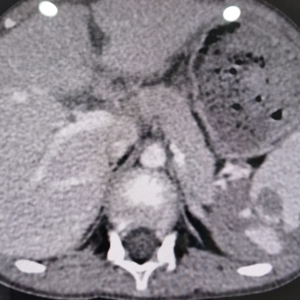

腹部彩超顯示

“脾臟破裂”

腹腔內(nèi)積血

打開腹腔后

腹腔內(nèi)

有約750ml的血性液體

脾的膈面近脾門處

有一長約5㎝的破裂傷口

出血不止